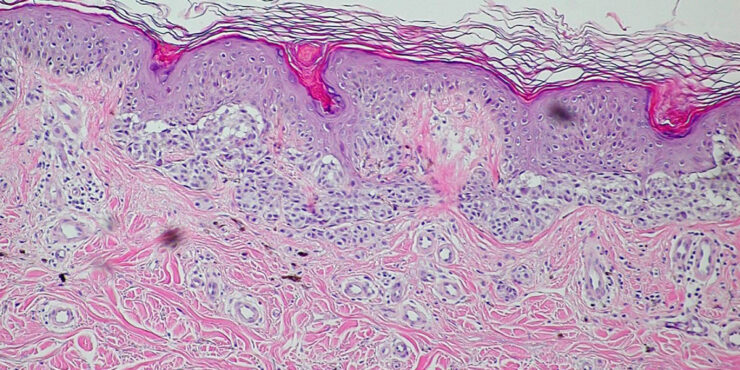

Compound Nevus =الوحمة المركبة